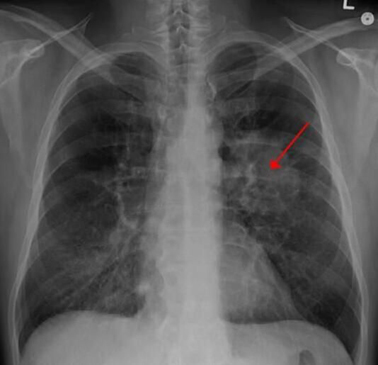

【3】Nat Med:重磅!科学家首次绘制出肺部肿瘤的完整细胞图谱!

近日,一项刊登在国际杂志Nature Medicine上的研究报告中,来自鲁汶大学等机构的科学家们通过研对数千个健康和癌变的肺部细胞进行研究,首次开发出了肺部肿瘤细胞的全面图谱,研究人员对52种不同的细胞类型进行了区分,研究结果表明,肺部肿瘤或许远比我们认为的要复杂的多,同时研究人员还希望基于本文研究结果来开发出有效治疗多种肺癌的新型疗法。

目前尽管科学家们在抗癌斗争中取得了巨大进展,但在细胞层面上对肿瘤进行科学理解还相对有限,随着诸如单细胞测序、大数据分析以及高级生物信息学技术的出现及发展,如今研究人员就能够在高分辨率模式下对微环境中的单一细胞进行研究,并且理解细胞的表型特征。